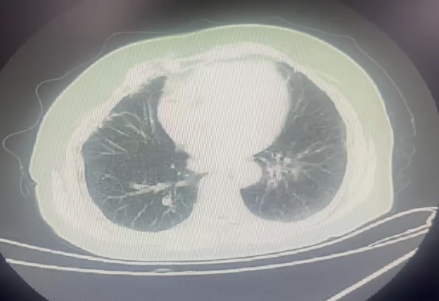

10月9日胸部 CT:双肺轻度间质改变伴纤维化。

11月18日胸部 CT:双肺新发弥漫磨玻璃影,纤维化较前加重。

CT 影像:11 月 27 日复查胸部 CT,可见双肺磨玻璃渗出影明显吸收,对比 11 月 18 日影像,肺部病变改善显著。

11月18日肺部 CT